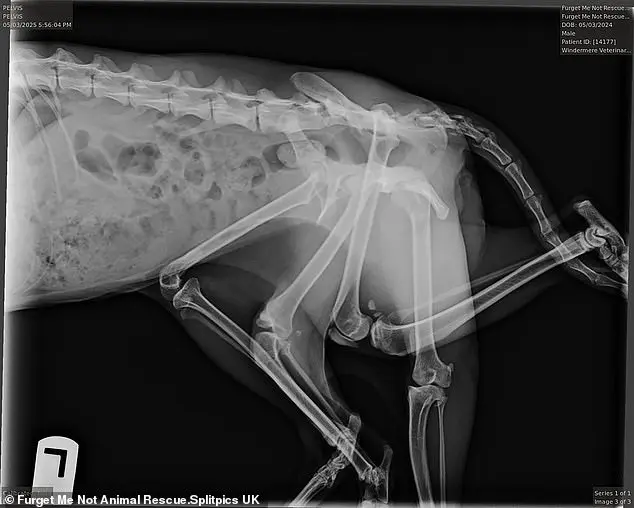

Ветеринары полагают, что лишние конечности Битси — это остатки близнеца, которого она поглотила в утробе матери.

К сожалению, три из шести лап кошки были нефункциональными и мешали ей двигаться.

Чтобы помочь животному, врачи удалили три лапки и часть таза.